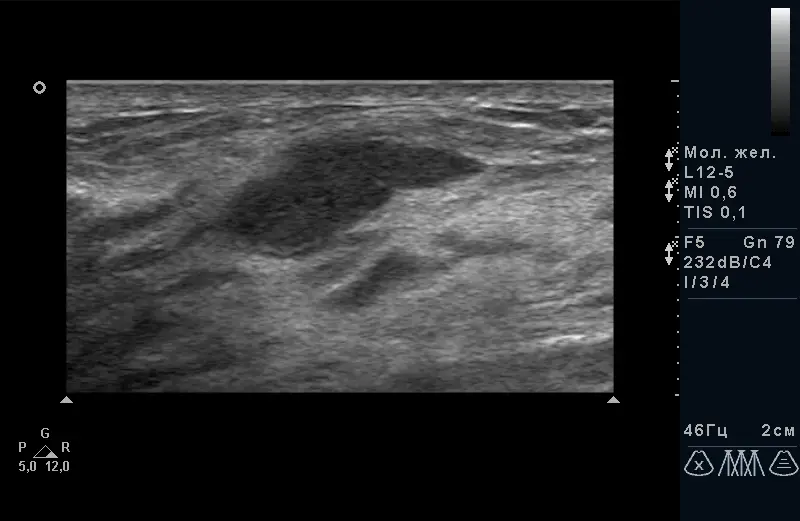

Рис.1. Фіброзно-кістозна мастопатія з кістозним компонентом. |